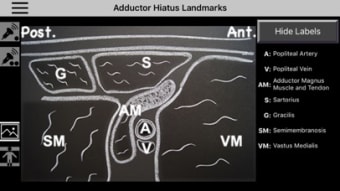

AnSo Anestesia Sonoanatomía es una aplicación para iPhone que proporciona una comprensión integral de la sonoanatomía relevante para el anestesista. Con más de 250 imágenes de ultrasonido y 1500 superposiciones de color de sonoanatomía, esta aplicación es un recurso conveniente diseñado para ayudar a los anestesistas a identificar la sonoanatomía común de manera eficiente en el tiempo dentro del ajetreado quirófano. Creado por anestesistas en ejercicio con interés en la enseñanza de la ecografía y la anestesia regional, AnSo proporciona múltiples ejemplos de la sonoanatomía ya que cada individuo es diferente.